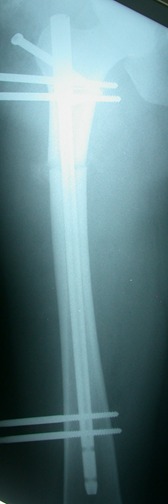

إطالة الطرف فوق تركيب مسمار نخاعي داخلي غيرذاتي  التطويل LON

هي تقنية جراحية تساعد المرضى الذين لا يرغبون في الحصول على تركيب جهاز تثبيت خارجي لفترة طويلة على عظامهم. ونستخدم أداة التثبيت الخارجية فقط خلال فترة الإطالة بينما يوجد مسمار نخاعي  داخل العظم ، ثم بعد الانتهاء من الإطالة نقوم بتثبيت  المسمار النخاعي داخل العظم ونقوم بإزالة المثبت الخارجي  ، بحيث يستطيع المسمار النخاعي حماية العظم الضعيف الذي تم تشكيله حديثًا حتى يتم إلتئامه  بالكامل في غضون 4إلي 5 أشهر.من مزايا هذه العملية أن فترة التثبيت الخارجي بأكمله يستغرق حوالي من 10إلي 12 أسبوعًا وأنه أرخص بكثير من القيام بالمسامير  النخاعيه الداخلية  ذاتية التطويل .

من عيوبها اننا نحتاج إلى اجراء عمليتان علي الاقل : واحدة لإدخال المسمار النخاعي وجهاز المثبت الخارجي والأخرى للتثبيت النهائي المسمار النخاعي وإزالة المثبت الخارجي بعد الانتهاء من الإطالة الكبري .

ميزتها أنها أرخص فى التكلفه من طريقة المسمار الداخلي بالريموت كنترول مع تقليص فترة التثبيت الخارجي .